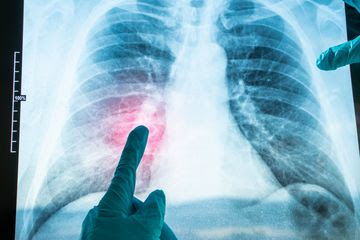

remehkan gejala ringan, karena pneumonia (radang paru-paru), salah satu bentuk

ISPA berat, menjadi penyebab kematian anak tertinggi di dunia menurut WHO.

Pneumonia